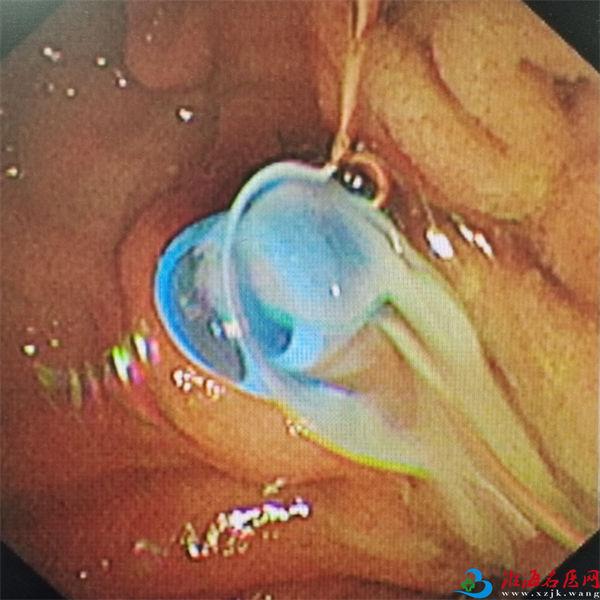

支架植入后见脓液流出

入院次日,在麻醉团队、内镜中心护士长曹琳琳及主管护师戴文帝的紧密协作下,陈新孚和副主任医师陈卓团队成功为李先生实施了ERC+内镜下胆管支架置入术+胆管冲洗术。术中,胆管支架的植入有效缓解了梗阻症状,大量脓液被引流而出,李先生的状况迅速好转。